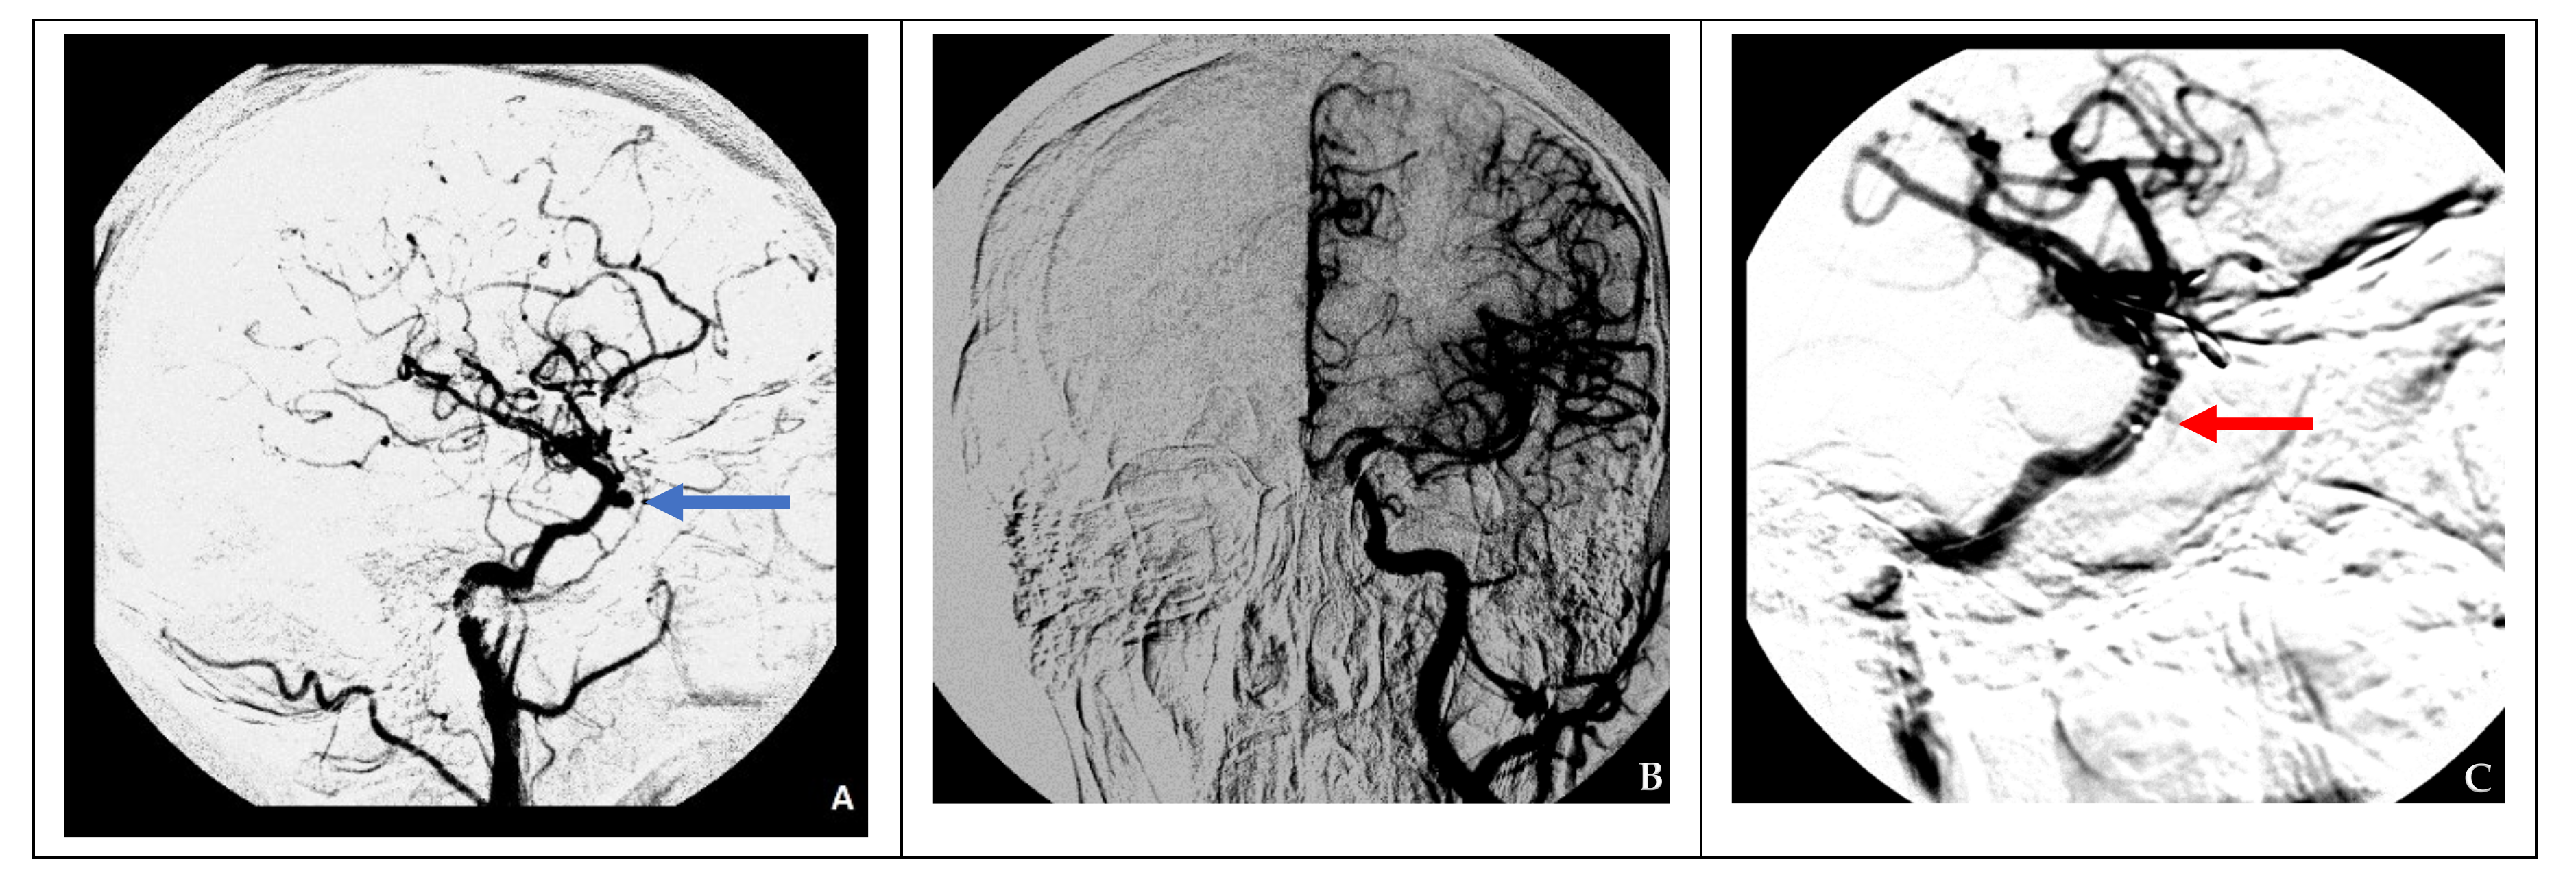

Figure 4. Endovascular treatment in a case of nonsufficient circulation (clinical case 4). (A) Formation of a false aneurysm at the level of the cavernous segment of the right ICA (blue arrow), (B) cerebral angiography of the left ICA indicating nonsufficient collateral circulation on the right side, and (C) installation of a stent graft (red arrow) at the site of the right ICA injury.

In the case of nonsufficient collateral circulation, the approach to closing the defect required maintaining the blood flow in the basin of the injured artery (reconstructive surgery) or replacing the blood flow (bypass) in the MCA basin on the ipsilateral side: in one case, the patient underwent a stent-graft procedure (Figure 4), and one patient underwent a high-flow bypass followed by ICA occlusion using microcoils (Figure 5).

It is significantly more challenging to close the ICA defect under nonsufficient collateral circulation conditions, leading to ischemic stroke after occlusion of the injured vessel. A stent graft can be used to close the defect while maintaining the lumen of the artery. This technique, however, is associated with several limitations: The stent can be placed over restricted sites of the ICA, in locations where no major collateral efferent arteries to the ICA exist; it cannot be placed at the bent standard anatomical curves of the ICA in the cavernous sinuses; and a stent graft is associated with a higher risk of thrombosis [7,13]. A high-flow bypass can compensate for cerebral blood flow in patients with nonsufficient collateral circulation to prevent ischemic complications. This approach was successfully used in the surgical treatment of giant ICA aneurysms [15,16,17].